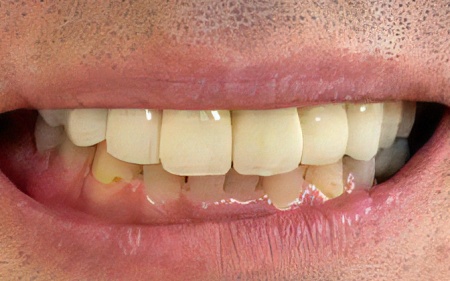

50代男性 バランスが崩れた噛み合わせをインプラント治療と被せ物治療で改善した症例

加えて、噛んだときに上下の歯の中心がずれており、顔貌のゆがみにもつながっています。

患者様は「見た目の自然さと、しっかり噛めることを重視したい」とのことで、欠損部の治療にはインプラントを選択され、合わなくなった被せ物や詰め物などの作り替えにも同意いただきました。

インプラントが骨にしっかりとなじんだことを確認したら、白くて強度の高い人工歯「ジルコニアクラウン」を装着しました。

最後に、見た目や噛み合わせに問題がないかを確認し、治療を終了しています。